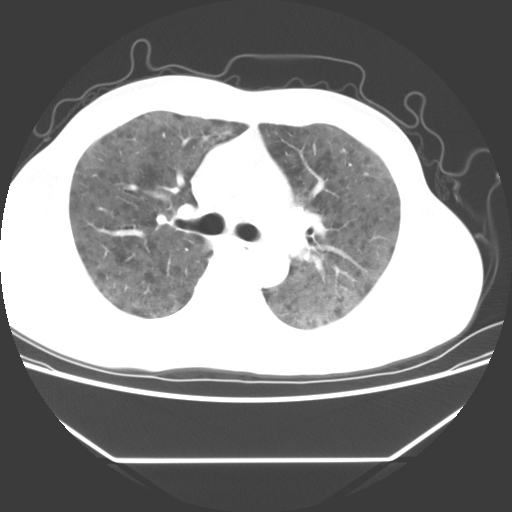

病人55岁,咳嗽,胸闷

忘了传病史了,病人55岁,咳嗽,胸闷

两肺部呈“毛玻璃”状改变,原因待查考虑感染性病变

病人是否发烧,两肺“磨玻璃”影,其间见空气支气管征和碎路石征。考虑肺泡蛋白沉着症。

两肺广泛对称磨玻璃样影,密度不均,考虑机遇性肺部感染。

双肺弥漫磨玻璃样病变,病史很重要。有感冒或发烧史,甲流不除外。无发烧可考虑肺泡蛋白沉积,但肺泡蛋白沉积边缘往往较清晰,与正常肺组织分界清晰

两肺弥漫间质性病变,考虑肺泡蛋白沉着症。建议进一步检查。

两肺“磨玻璃”影,其间见空气支气管征和碎路石征。考虑肺泡蛋白沉着症。